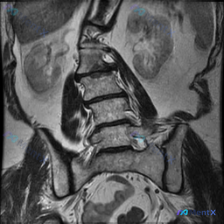

这张腰椎MRI冠状位只看到侧弯?别忘了这两个致命性盲区

整理到一张腰椎MRI冠状位T2加权像的资料,核心表现是腰椎有明显向左侧弯,椎间隙高度基本还在,但椎体边缘有毛糙/增生样信号改变。

第一眼很容易往「退行性脊柱侧弯」走,但仔细看分析报告里特意提了两个容易漏的方向——有没有可能是感染或者肿瘤?

📋答案:基于现有单张腰椎MRI冠状位T2加权像,**结构性腰椎侧弯**是明确的影像学表现;但从临床风险优先级排序:

1. 需优先排查隐匿性感染(如脊柱结核)或肿瘤等致命性疾病,其次考虑重度退行性脊柱侧弯。